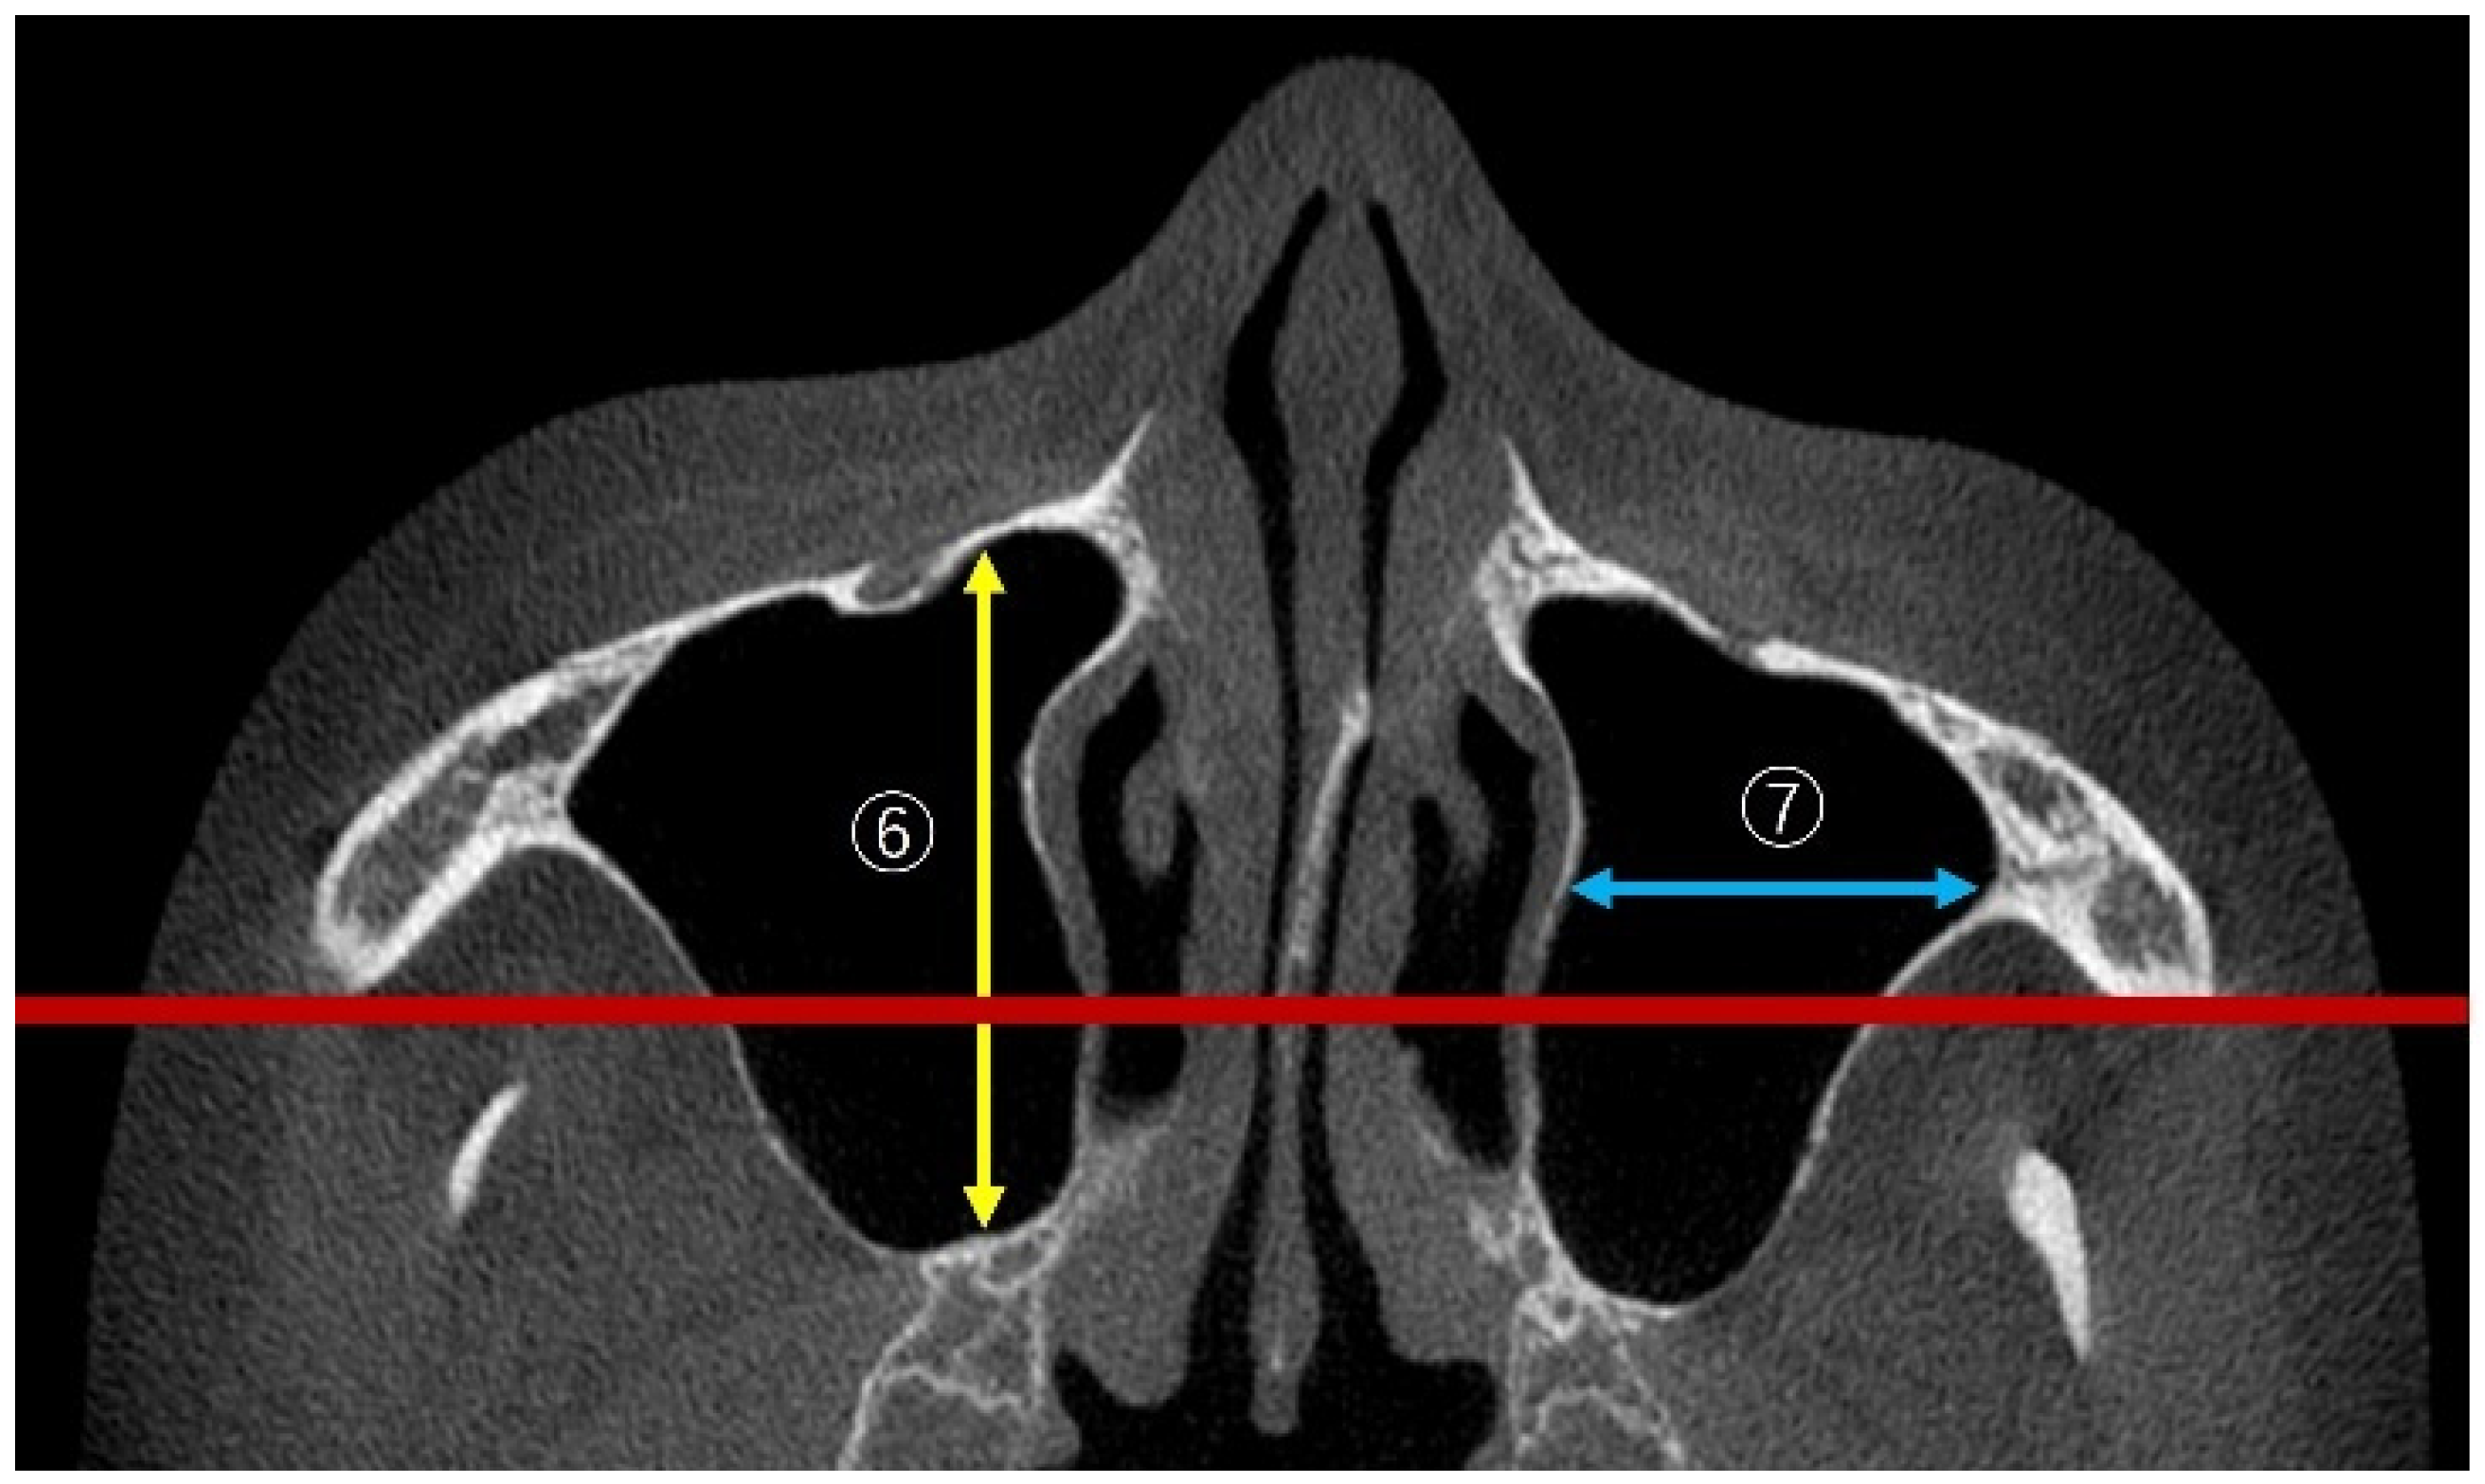

2.2. Measurement Method Using CBCT Images

2.3. Measurement Items

2.3.4. Linear Measurements of Maxillary Sinus Length